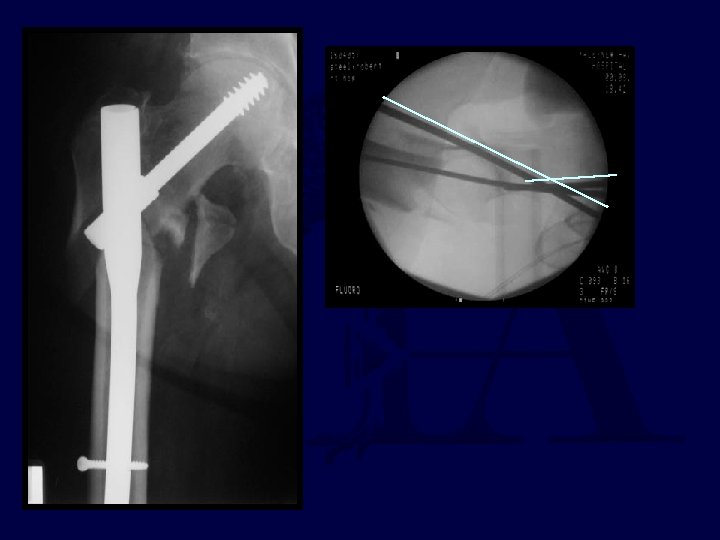

71 yo renal txplnt pt c CHF What to do? ?

If my patient, I would use: 1. Hip screw and sideplate 2. Hip screw and IM nail (TFN) 3. Reconstruction Nail (2 proximal medullary-cephalic screws) 4. Blade Plate 5. Other

percutaneous reduction

Uneventful Healing, WBAT 6 wks 12 wks